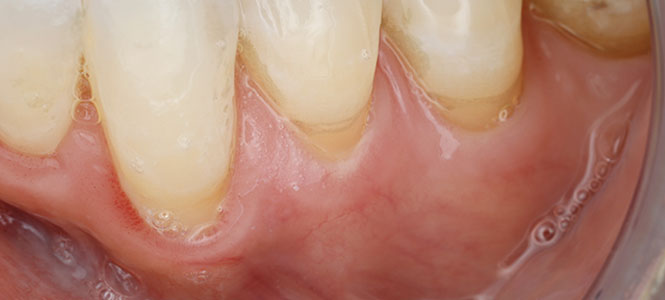

A healthy smile depends on strong, protective gums. But when gum tissue begins to recede, the roots of your teeth are left exposed. This can cause sensitivity, make your teeth appear longer, and increase your risk of decay and tooth loss. For many people, gum recession happens so gradually that they don’t notice until discomfort—or even damage—appears.

Exposed tooth roots are not just a cosmetic concern. Left untreated, gum recession can lead to:

Increased tooth sensitivity to hot, cold, or sweet foods

Higher risk of cavities on the exposed roots

Progressive bone loss around the affected teeth

Loosening and eventual loss of teeth